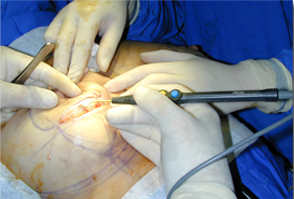

可實現(xiàn)切割,凝血同步。

適用于良好控制的止血。

適合于要求良好止血的切割。